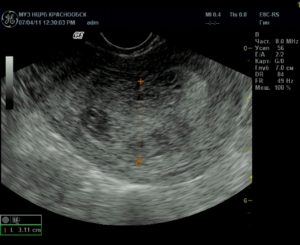

- Эндометрия (его толщину: слой более 26 мм требует оперативного вмешательства; наличие образований, в том числе остатки плодного яйца: на УЗИ – темное круглое образование в толще слоя).

Проводится визуальный осмотр шейки матки и пальпация. Внутренний зев ее будет расширен, плодный остаток в наличии. УЗИ определит его объем и локализацию, а также общее состояние репродуктивных органов. Биохимический анализ крови расскажет о функционировании органов и систем пациентки.